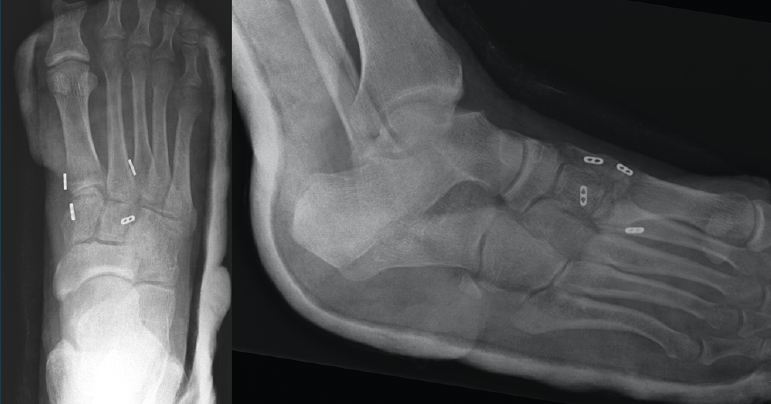

Se realiza la intervención quirúrgica a las 8 semanas con reducción abierta mediante abordaje dorsomedial confirmando la inestabilidad articular y realizando una estabilización con sutura intraósea con botón de C1-M2. Se comprueba que aún persistía cierta inestabilidad en el plano frontal, por lo que se decide poner otro dispositivo de C2 a M1. Se inmoviliza con una férula suropédica y se indica descarga (Figura 2).

Figura 2. Caso 1. Resultados radiográficos posquirúrgicos.

Figura 4. Caso 2. Radiografías lateral y anteroposterior sin carga de control tras la cirugía con fijación no rígida.